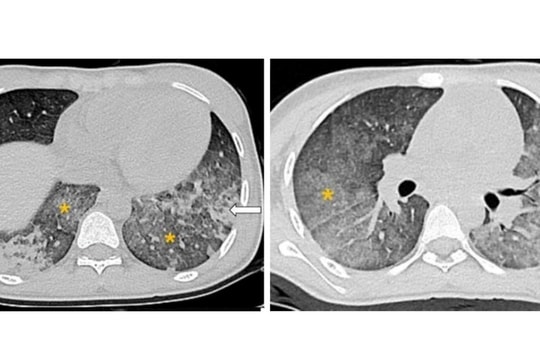

Trung tâm Nhi khoa - Bệnh viện Bạch Mai vừa thông tin về một trường hợp bệnh nhi nữ 14 tuổi được cứu sống ngoạn mục sau khi gặp biến chứng chảy máu phế nang lan tỏa (DAH) khi mắc bệnh lupus ban đỏ hệ thống (SLE).